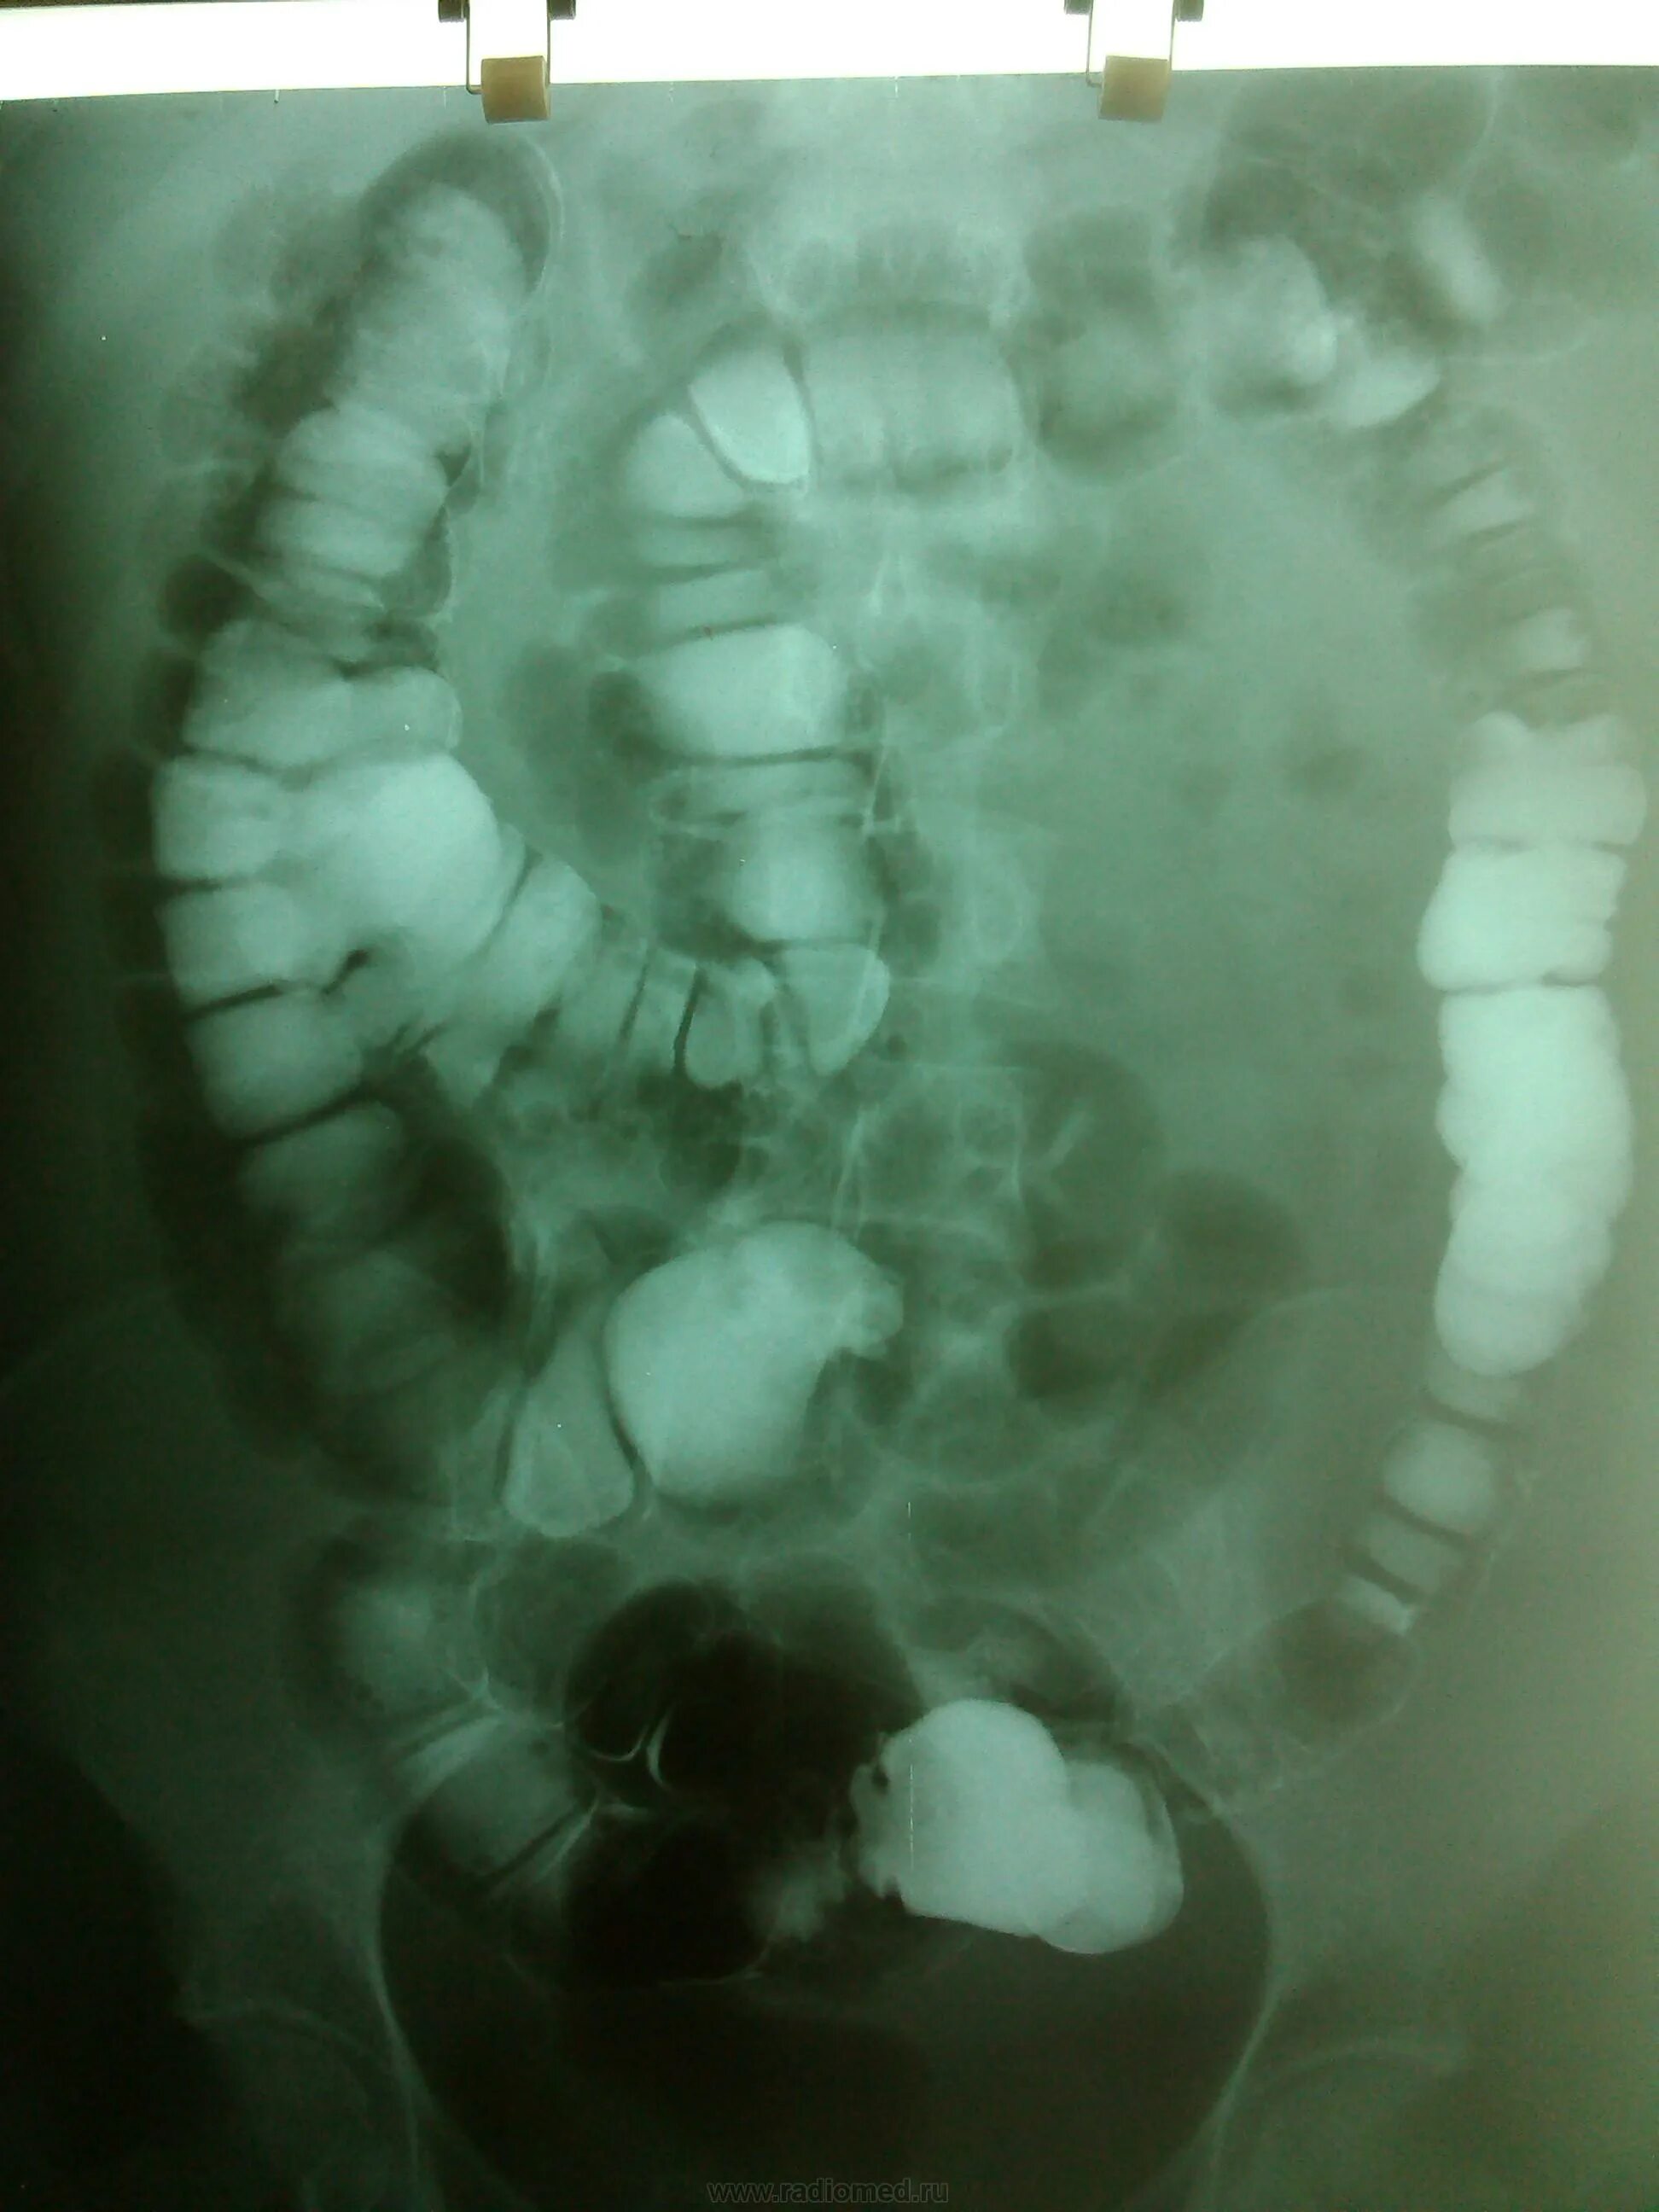

Долихосигма кишечника у ребенка